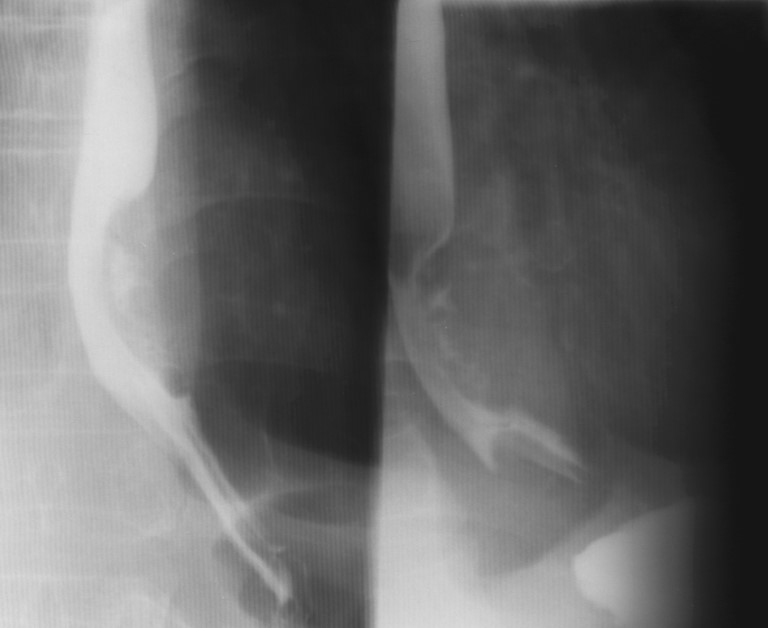

What is the radiographic appearance of infiltrative gastric carcinoma?

Thickened walls, narrowed lumen, rigid non-contracting 'fixed stomach', loss of rugal folds.

What is the hourglass stomach?

Circumferential involvement causing mid-gastric narrowing.

What is the radiographic appearance of proliferative type of gastric carcinoma?

Polypoid mass projecting into the lumen; may mimic ulcer.

What are the best imaging studies for gastric carcinoma?

UGI for detection; CT for staging, treatment, and follow-up.